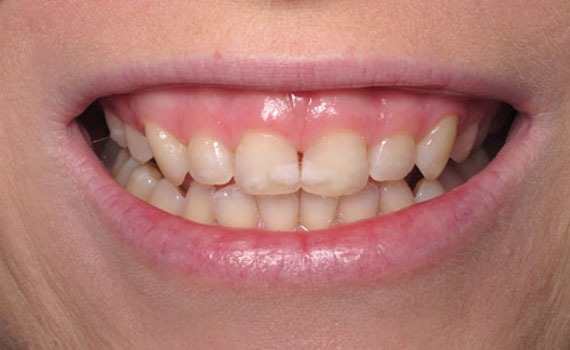

Ortodonti

Diş çapraşıklıkları çocukluk döneminde süt dişlerin yerini asıl dişlerin alması ile başlayan bir süreçtir.